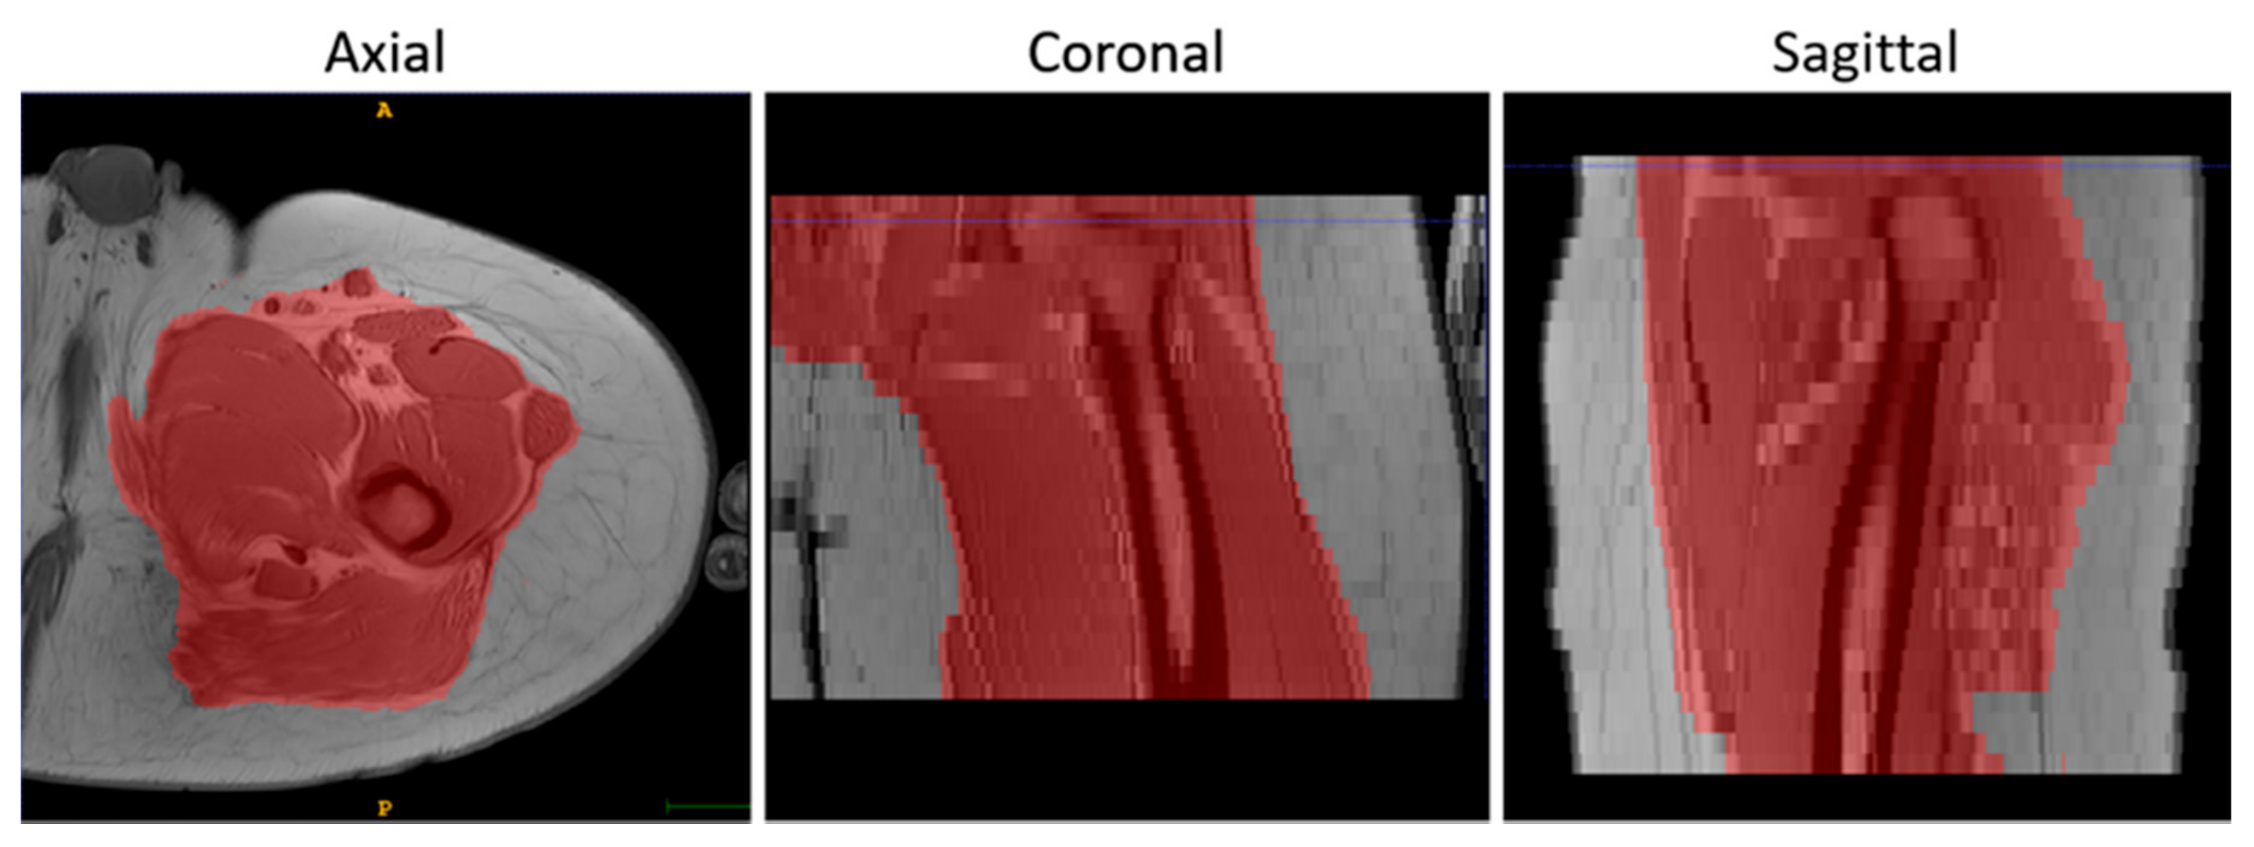

• To suppress the contribution of the subcutaneous fat, muscle volumes were selected using the semi-automatic segmentation tool of ITK-Snap (v3.8.0) [34] before registration and used as masks to calculate the similarity metric, as shown in Figure 2.

Figure 2. An example of the results of the masking step on T1-w MR images in 3 orthogonal views.